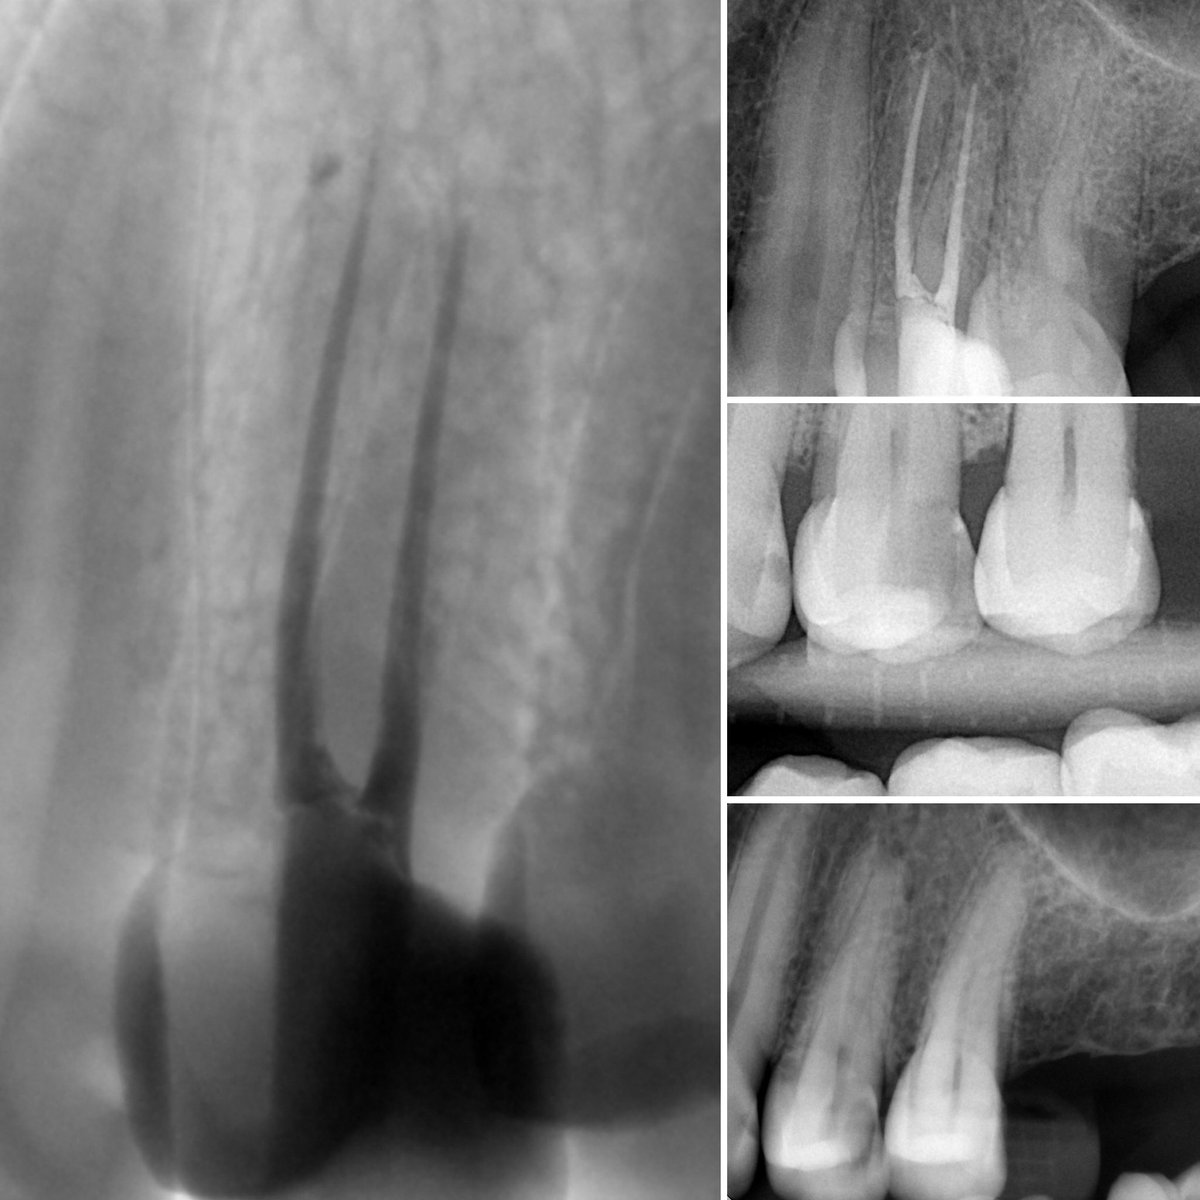

Dx:

24: Symptomatic irreversible Pulpitis w/ SAP

TX:

Non-Surgical RCT (One Visit)